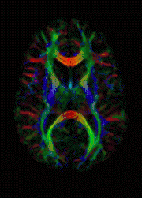

| Diffusion tensor | DTI | Mainly tractography (pictured) by an overall greater Brownian motion of water molecules in the directions of nerve fibers.[21] |

Diffusion weighted

Diffusion MRI measures the diffusion of water molecules in biological tissues.[41] Clinically, diffusion MRI is useful for the diagnoses of conditions (e.g., stroke) or neurological disorders (e.g., multiple sclerosis), and helps better understand the connectivity of white matter axons in the central nervous system.[42] In an isotropic medium (inside a glass of water for example), water molecules naturally move randomly according to turbulence and Brownian motion. In biological tissues however, where the Reynolds number is low enough for laminar flow, the diffusion may be anisotropic. For example, a molecule inside the axon of a neuron has a low probability of crossing the myelin membrane. Therefore, the molecule moves principally along the axis of the neural fiber. If it is known that molecules in a particular voxel diffuse principally in one direction, the assumption can be made that the majority of the fibers in this area are parallel to that direction.

The recent development of diffusion tensor imaging (DTI)[43] enables diffusion to be measured in multiple directions, and the fractional anisotropy in each direction to be calculated for each voxel. This enables researchers to make brain maps of fiber directions to examine the connectivity of different regions in the brain (using tractography) or to examine areas of neural degeneration and demyelination in diseases like multiple sclerosis.